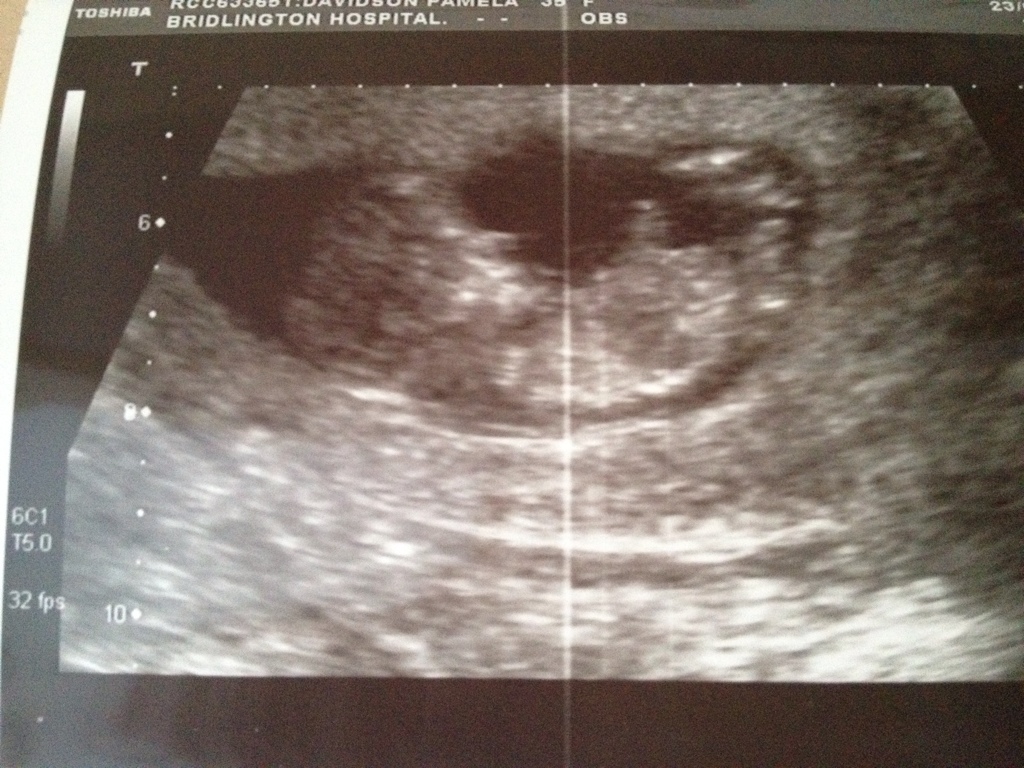

I'm a bit new to this, buti can't see anything nub like. Might be able to guess from the skull, I'm no expert on this either lol but I would say boy x

12w 1d, i forgot to mention , hoping for boy, but im not lucky x

I guess boy. looks like an upward-pointing nub. good luck! xo

i would say absolutely boy!! looks exactly like my ds 2 nub!

Iv circled and squared bits from my u/s picture , is one of these the nub? X thanks again x